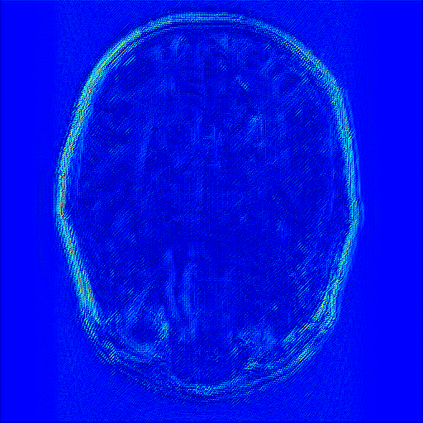

Reconstructing magnetic resonance (MR) images from undersampled data is a challenging problem due to various artifacts introduced by the under-sampling operation. Recent deep learning-based methods for MR image reconstruction usually leverage a generic auto-encoder architecture which captures low-level features at the initial layers and high?level features at the deeper layers. Such networks focus much on global features which may not be optimal to reconstruct the fully-sampled image. In this paper, we propose an Over-and-Under Complete Convolu?tional Recurrent Neural Network (OUCR), which consists of an overcomplete and an undercomplete Convolutional Recurrent Neural Network(CRNN). The overcomplete branch gives special attention in learning local structures by restraining the receptive field of the network. Combining it with the undercomplete branch leads to a network which focuses more on low-level features without losing out on the global structures. Extensive experiments on two datasets demonstrate that the proposed method achieves significant improvements over the compressed sensing and popular deep learning-based methods with less number of trainable parameters. Our code is available at https://github.com/guopengf/OUCR.